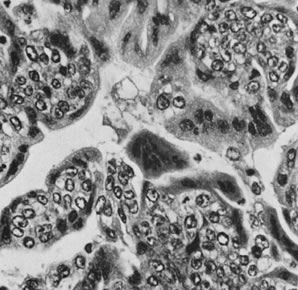

This tumor, which was originally called endodermal sinus tumor, is characterized by a variety of patterns and cell types that have been interpreted as simulating those of yolk sac epithelium and its derivatives.43,44 The neoplasm accounts for approximately 20% of primitive germ cell tumors of the ovary. The endodermal sinus tumor is the first described and the most common subtype of yolk sac tumor. It is characterized by a network of spaces lined by immature epithelial cells (reticular pattern) and occupied focally by single papillary projections, which have been designated Schiller-Duval bodies (Fig. 18). These structures, which contain single central blood vessels and are lined by neoplastic epithelium, resemble to some extent downgrowths of yolk sac epithelium into the extraembryonic mesenchyme of the labyrinthine placenta of the rodent, known as endodermalsinuses. Schiller-Duval bodies are present in most endodermal sinus tumors but may be rare or absent; in such cases, the tumor may have a pure reticular pattern, which merges in many cases with microcystic foci. Another microscopic feature of the endodermal sinus tumor is the presence of intracellular hyaline bodies (Fig. 19). The yolk sac nature of the tumor is confirmed by the immunohistochemical demonstration of alpha-fetoprotein in some of the tumor cells and by the presence of elevated levels of this oncofetal protein in the serum. A more mature form of yolk sac tumor is characterized by a polyvesicular vitelline pattern, in which vesicles lined by columnar-to-flattened epithelium are present in a cellular stroma. These vesicles often show an eccentric constriction, which has been interpreted as a recapitulation of the formation of the secondary or definitive yolk sac from the primary yolk sac (Fig. 20). In the normal embryo, the primary yolk sac becomes vestigial, and the secondary yolk sac develops into the gastrointestinal tract and its appendages, such as the liver. The polyvesicular vitelline pattern is usually a minor component of a yolk sac tumor, but in rare cases, it predominates. Other patterns are papillary and solid. In addition, in keeping with the role of the yolk sac in the formation of the gastrointestinal tract and its appendages, rare yolk sac tumors have a distinctive glandular pattern with cribriform areas and are composed of cells that resemble those of the primitive intestinal tract. These tumors are called glandular yolk sac tumors45; some of them simulate closely endometrioid adenocarcinomas with or without squamous differentiation (endometrioid-like yolk sac tumors) and can be distinguished from true endometrioid tumors by the demonstration of alpha-fetoprotein in the cytoplasm of their neoplastic cells.46 A final form of yolk sac tumor is the hepatoid form, which is indistinguishable from a hepatocellular carcinoma of the liver and is also associated with alpha-fetoprotein production.47 Gross examination of a yolk sac tumor reveals a solid mass that typically shows areas of necrosis, gelatinous degeneration, hemorrhage, and often cyst formation (Fig. 21). Rupture has been reported in approximately one third of cases.

Fig. 18. Endodermal sinus tumor, reticular pattern with Schiller-Duval body (magnification, ×300).(Scully RE: Germ cell tumors of the ovary and fallopian tube. In Meigs JV, Sturgis SH [eds]: Progress in Gynecology, Vol 4. New York, Grune & Stratton, 1963, by permission.)

Fig. 19. Endodermal sinus tumor with hyaline bodies (magnification, ×750).(Serov SF, Scully RE, Sobin LH: Histological Typing of Ovarian Tumours. Geneva, World Health Organization, 1973.)

Fig. 20. Endodermal sinus tumor, polyvesicular vitelline pattern (magnification, ×190). Secondary yolk sac at right is budding from larger primary yolk sac.(Serov SF, Scully RE, Sobin LH: Histological Typing of Ovarian Tumours. Geneva, World Health Organization, 1973.)